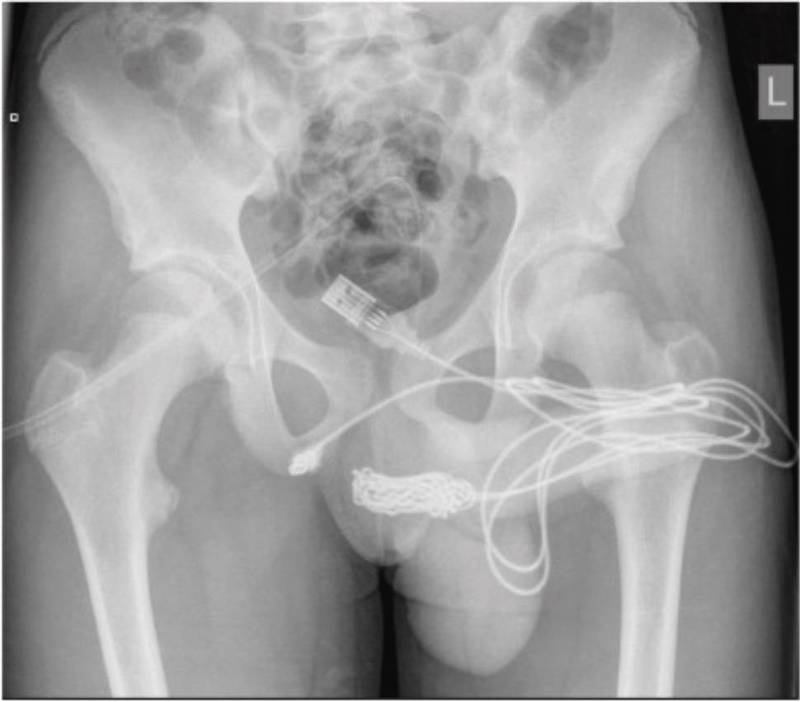

在安排鼠蹊部X光檢查,以確認轉接線打結位置後,外科醫師將陰莖和陰囊周圍的肌肉切開,並切斷轉接線打結處後順利將其去除。該名少年術後觀察也相當順利,僅住院2天就康復出院。